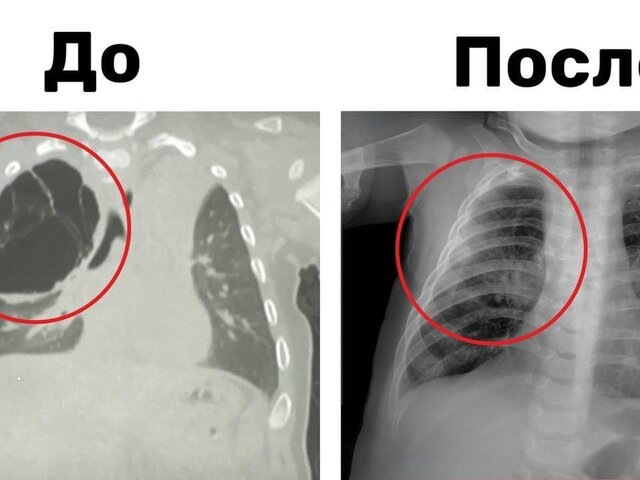

Подмосковные хирурги удалили ребенку кисту легкого размером 15 сантиметров

По информации ведомства, в результате обследования врачи обнаружили у ребенка 15-сантиметровую кисту, занимавшую значительную часть верхней доли правого легкого. Новообразование сдавливало здоровую ткань органа, что мешало его полноценному росту и развитию.

Хирурги приняли решение о проведении торакоскопической операции, в ходе которой им смогли удалить кисту без внешних разрезов. Продолжительность вмешательства составила около часа. В данный момент мальчик чувствует себя хорошо и уже выписан домой.